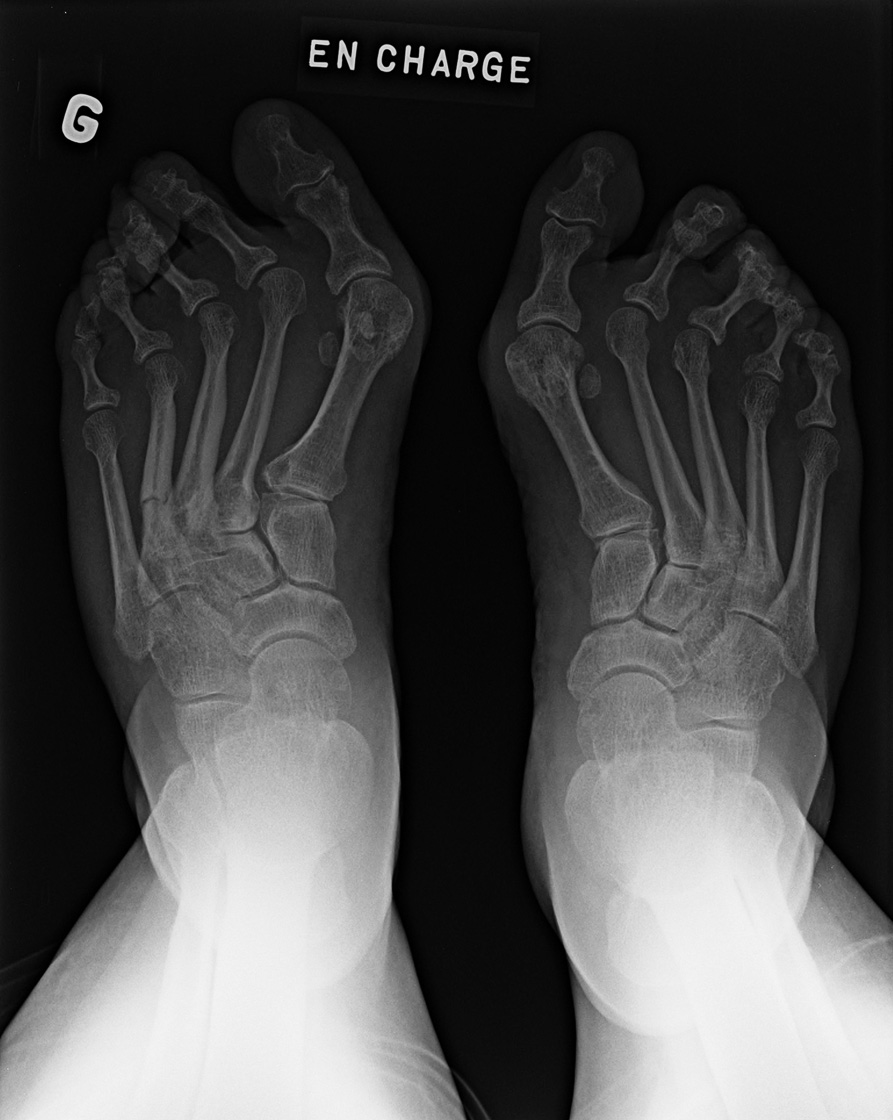

Standing view of the feet

• Anteroposterior

• Lateral

• Oblique

• Standing view of the feet